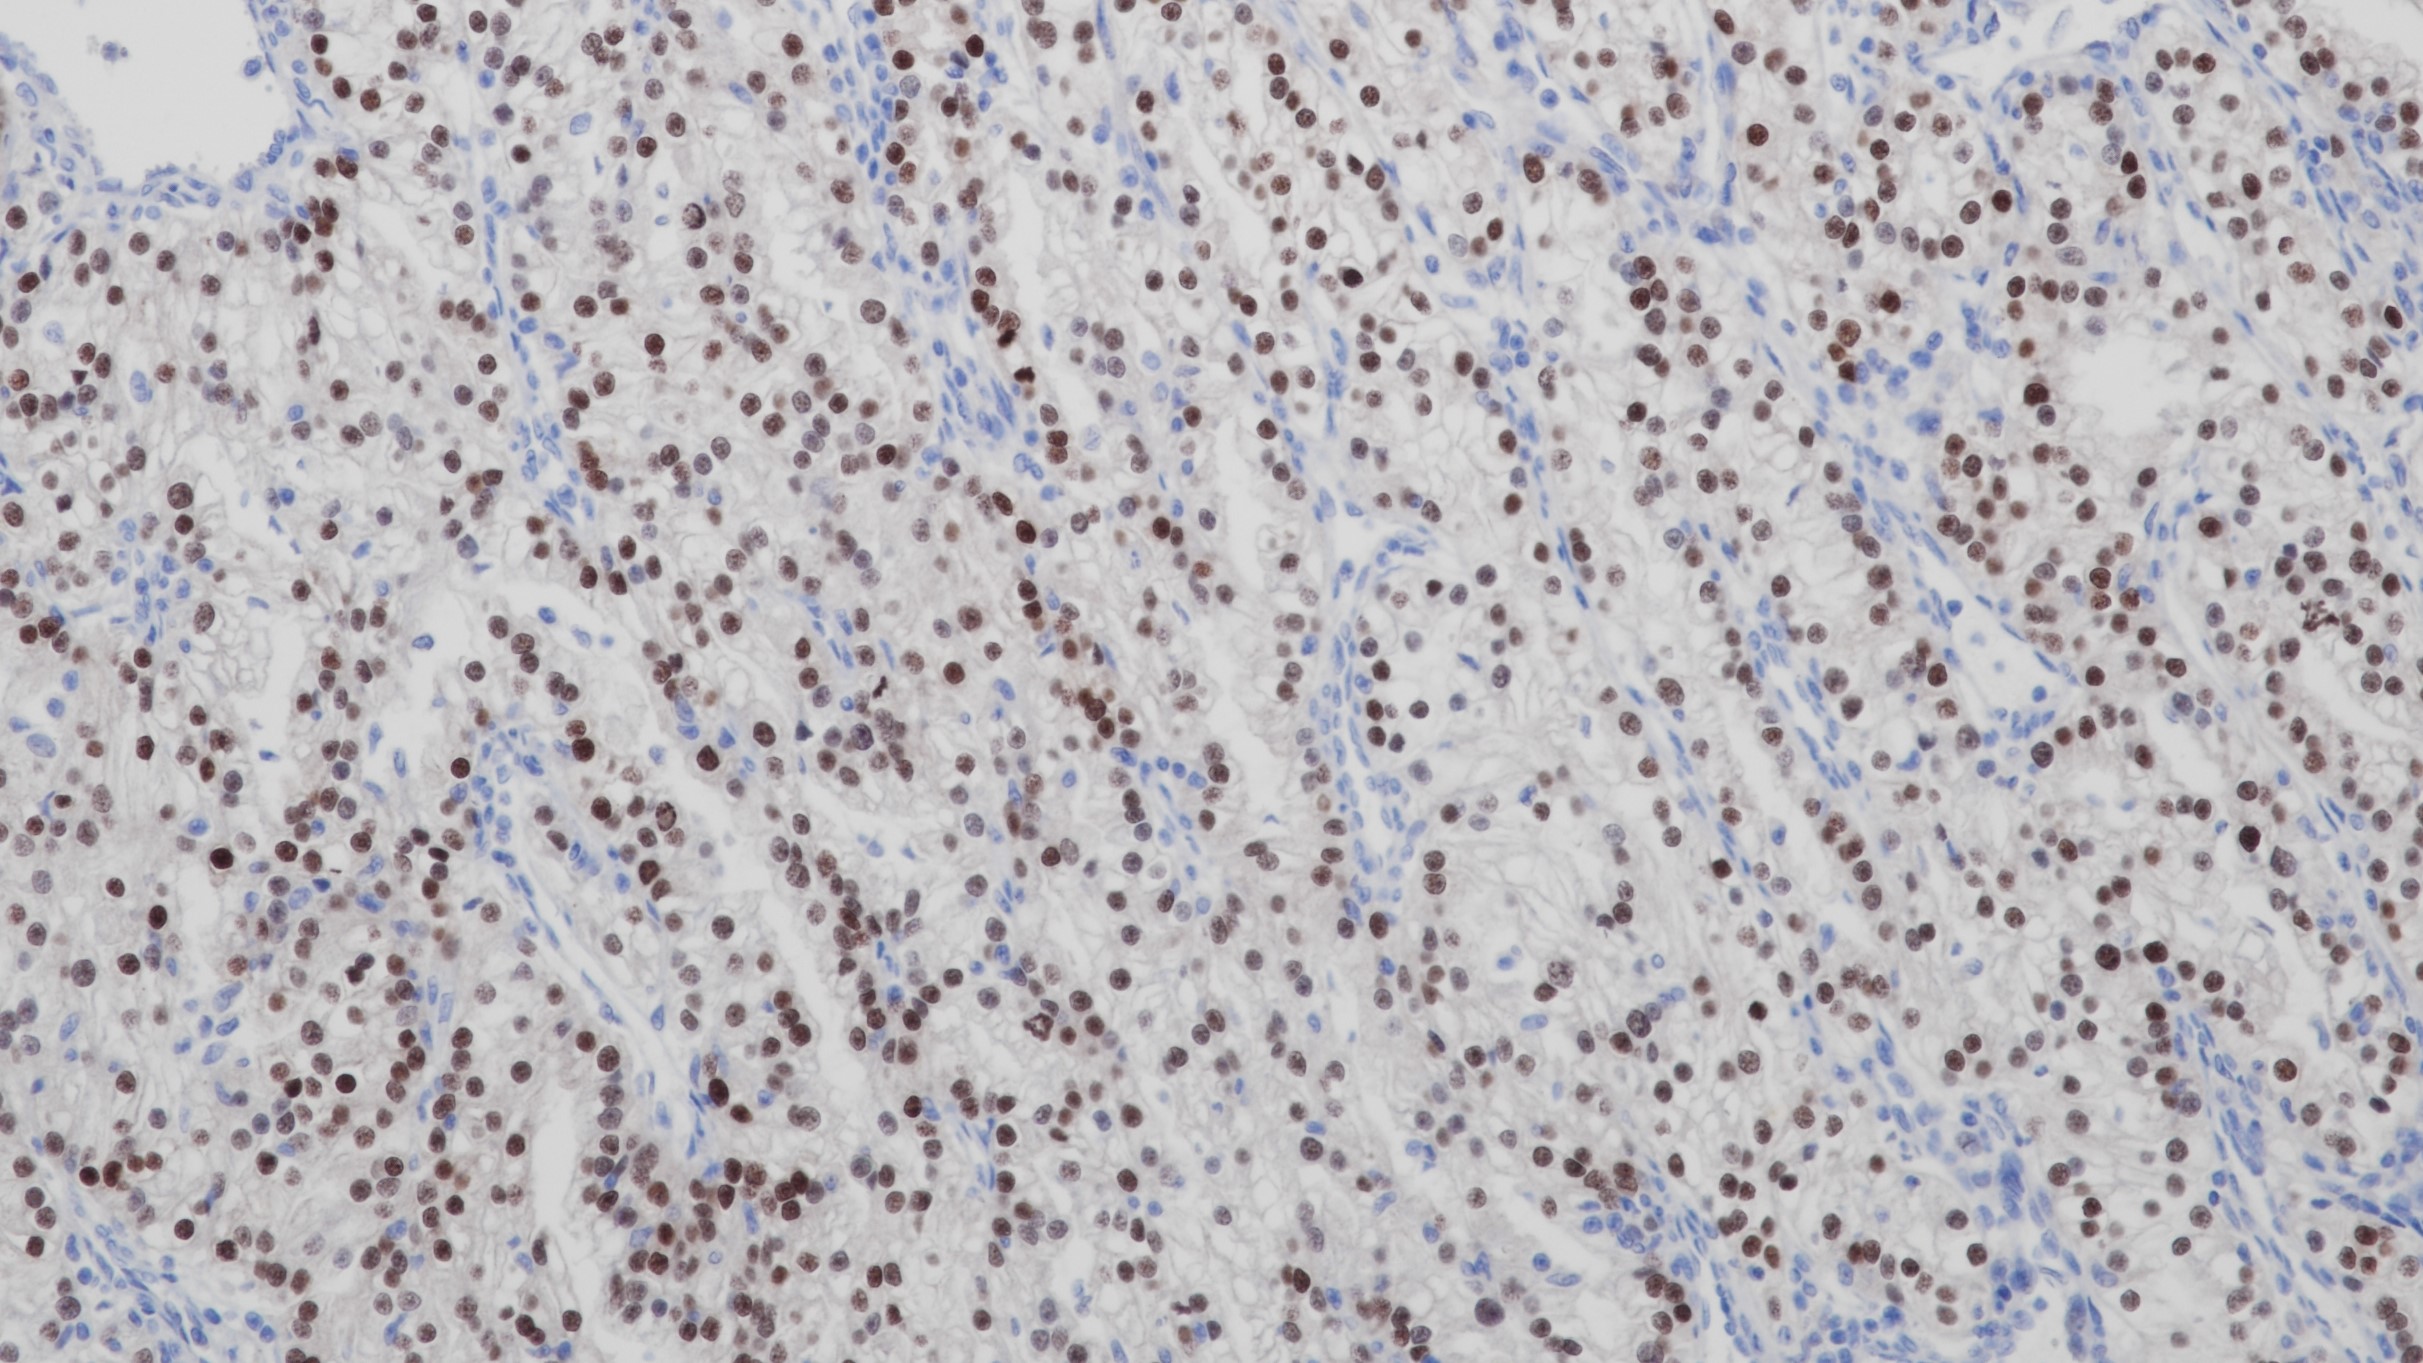

CD2主要存在于成熟的T细胞和NK细胞膜表面, 而B细胞通常不表达,可标记正常T细胞及其相关肿瘤,如前T细胞淋巴瘤、边缘T细胞淋巴瘤和间变大细胞淋巴瘤的诊断与研究。

阳性对照

T细胞淋巴瘤